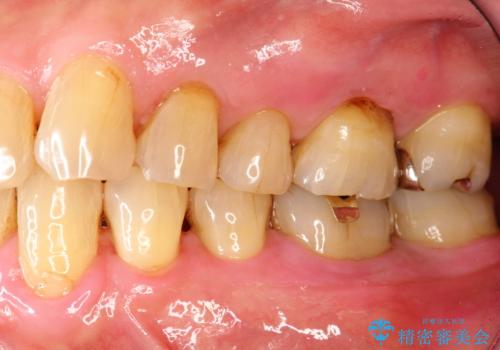

- 2カ月ごとにメンテナンスにいらしている方です。染め出しをしての歯磨きチェックとPMTC30分コースを行いました。

口腔内にはたくさんの細菌がいるため、ヌルヌルとしたプラーク(歯垢)が自然に歯の表面に付きます。

このプラーク(歯垢)にはたくさんの細菌が潜んでおり、虫歯や歯周病・口臭などの最大の原因です。そのため、毎日の歯磨きでプラーク(歯垢)をキレイに取り除くことが、健康な歯を保つためには欠かせません。